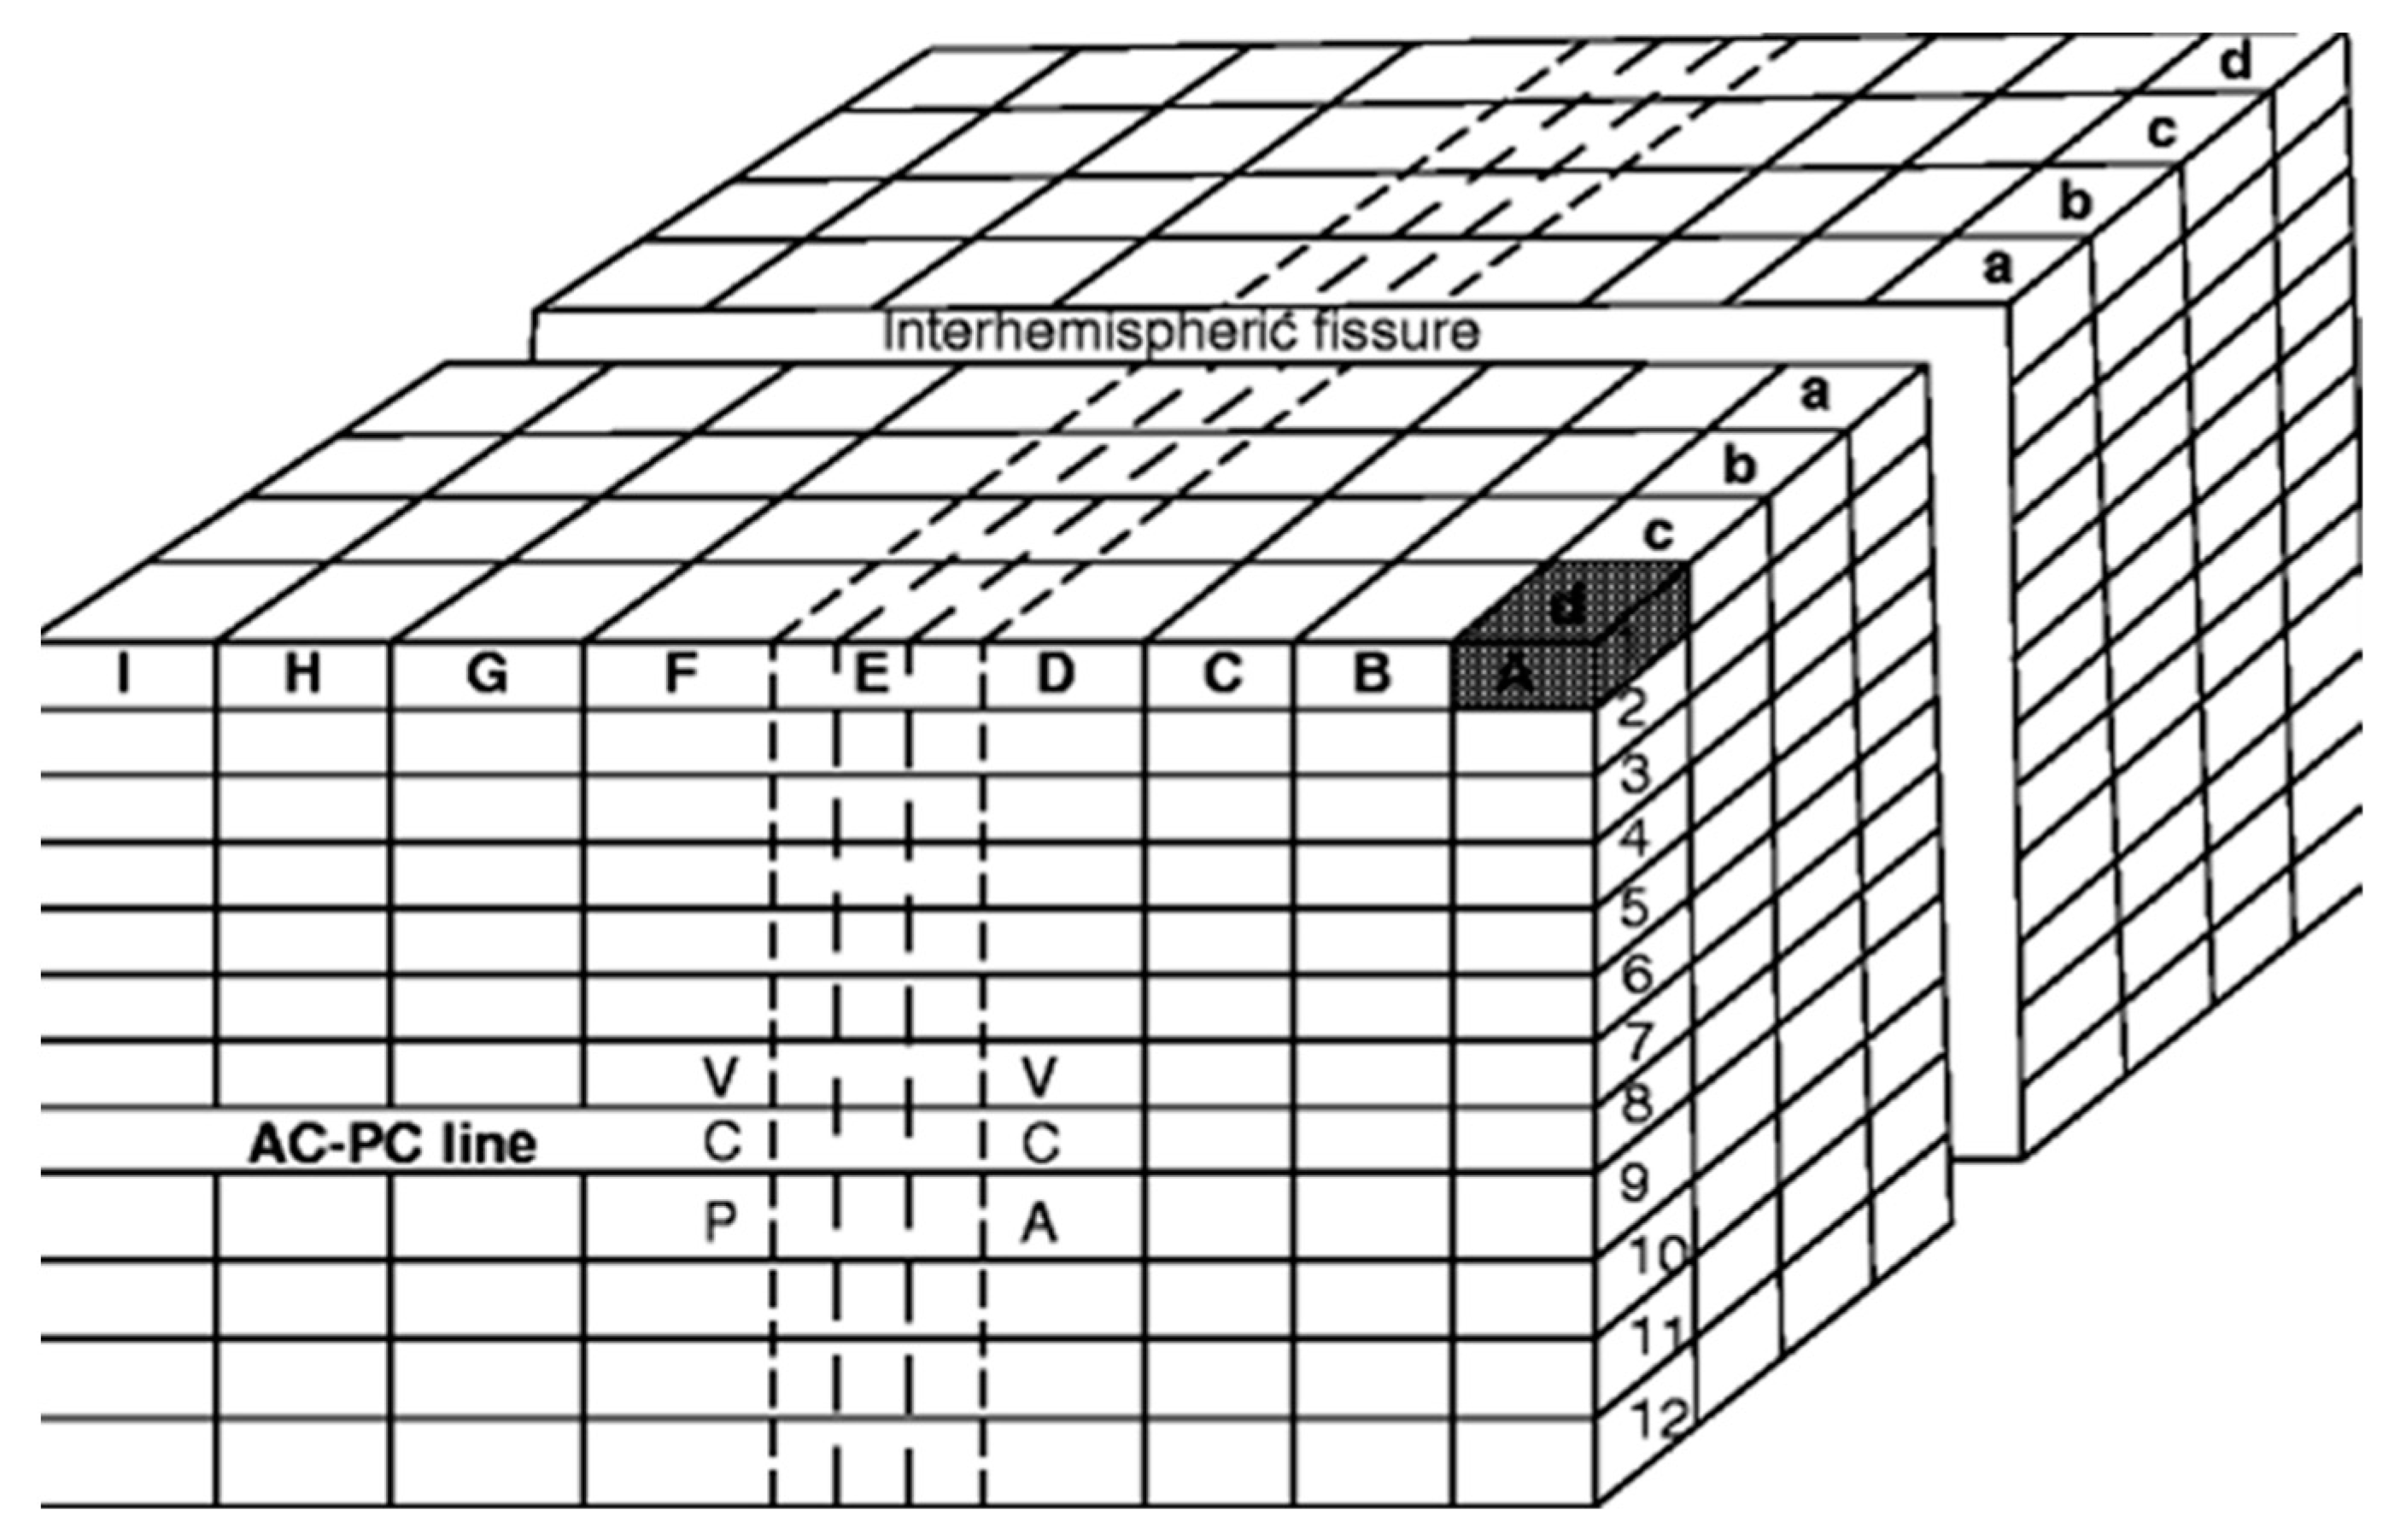

4. The Proportional System of Talairach

- Talairach, J.; David, M.; Tournoux, P.; Corredor, H.; Kvasina, T. Atlas d’Anatomie Stereotaxique. Repérage Radiologique Indirect Des Noyaux Gris Centraux Des Régions Mésencéphalo-Sous-Optique et Hypothalamique de l’homme; Masson: Paris, France, 1957. [Google Scholar]

- Talairach, J.; Tournoux, P. Co-Planar Stereotaxic Atlas of the Human Brain: 3-Dimensional Proportional System: An Approach to Cerebral Imaging; Thieme: Stuttgart, Germany, 1988. [Google Scholar]

- Nowinski, W.L. Modified Talairach Landmarks. Acta Neurochir. 2001, 143, 1045–1057. [Google Scholar] [CrossRef]

7.2. The Talairach–Nowinski System